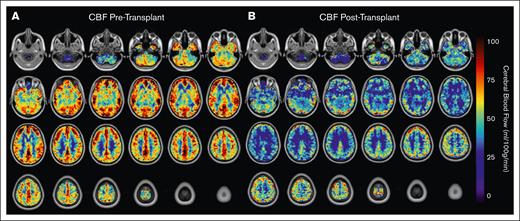

Healthy control (n = 28) CBF mean values were 47.5 ± 4.4 mL/100 g per minute; in adults with SCD, pretransplant mean CBF was elevated relative to that of control participants (P = .004) and significantly decreased from before transplant (CBF = 69.1 ± 24.8 mL/100 g per minute) to after transplant (CBF = 48.2 ± 13.9 mL/100 g per minute; P = .003; Figure 1A). Mean gray matter CBF maps are presented in Figure 2. After haplo-BMT, adults with SCD did not show significant CBF differences compared with control participants (P = .78; Figure 1B).

CBF changes before and after transplant shown in axial blood flow maps in MNI space. Ascending axial slices of CBF (mL/100 g per minute) maps averaged across participants with SCD before (A) and after (B) HSCT. Maps are shown overlayed on standard (Montreal Neurological Institute) space anatomical T1 images.